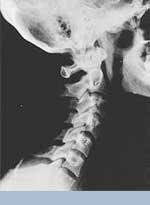

This is a side x-ray view of the neck. As with all the pictures you will see on this page, the patient is looking to the right of the screen, so you are viewing the right side of their neck. We will call this picture a "near normal" spine. Compare this spine with the ones you will see below on this page. Notice the normal forward curve of the neck. This curve helps absorb shock. Notice how each of the disc spaces between C2 (second bone in neck) and C7 are thick and even, this again is normal. Also notice how the front portions (right on the x-ray) of each of the vertebrae (called the 'body' of the vertebrae) are fairly square with clear and well defined borders. This type of arrangement is normal in the neck. Normal vertebrae in other parts of the spine also have similar characteristics to what we see here. When subluxations occur and are left uncorrected, ongoing relentless changes occur that result in damage to the structure and function of the spine along with nerve damage and the resulting problems caused from improper nerve supply.